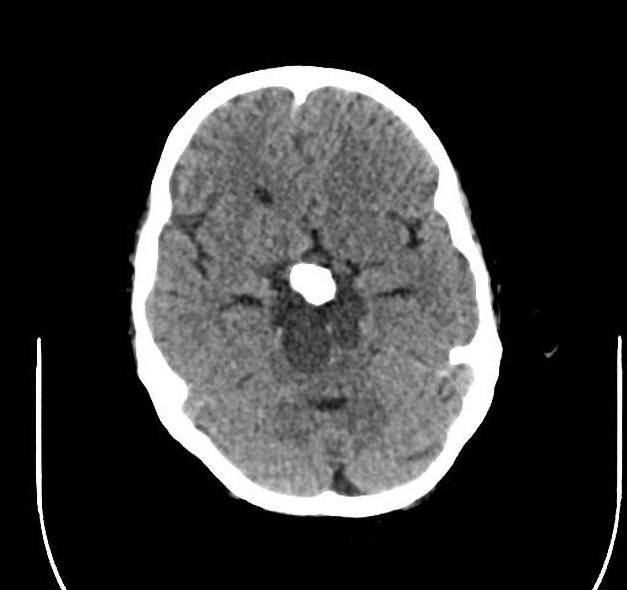

U sọ hầu

» Thông tin: Nam giới – 30 tuổi.

» Lâm sàng: Đau đầu.